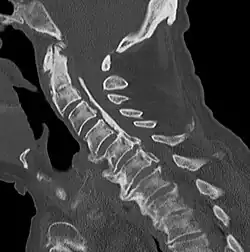

Das Ligamentum longitudinale posterius („hinteres Längsband“), bei Tieren als Ligamentum longitudinale dorsale („rückenseitiges Längsband“) bezeichnet, ist ein längs verlaufendes Band der Wirbelsäule. Es besteht aus straffem kollagenem Bindegewebe und verbindet die einzelnen Wirbelkörper an deren Hinterseite miteinander und liegt somit innerhalb des Wirbelkanals. Es ist mit den Wirbelkörpern nur lose verbunden, dafür fest mit den Bandscheiben. Es beginnt am zweiten Halswirbel und reicht bis zum Kreuzbein. Vom zweiten Halswirbel geht es kopfwärts in die Membrana tectoria über, die bis zum Hinterhauptsbein reicht.